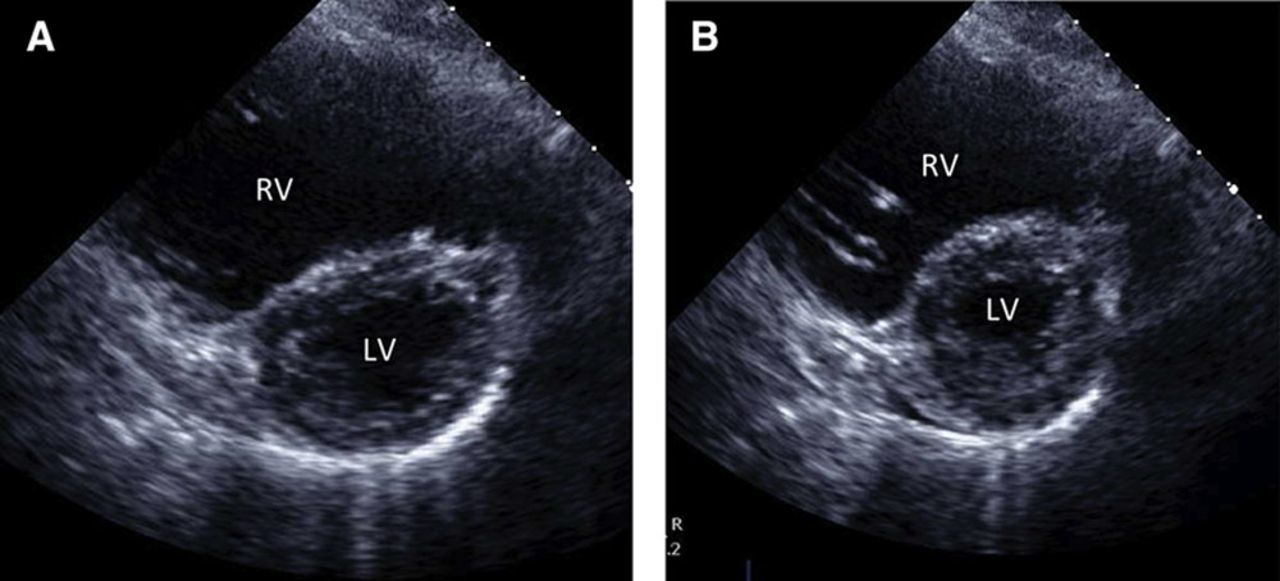

What is wrong here

Left ventricle hypertrophy

Right ventricle hypertrophy